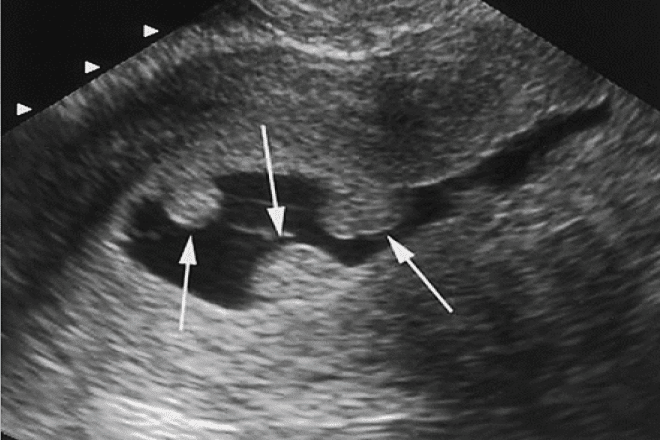

18

Q

Qual o diagnostico

A

pólipo